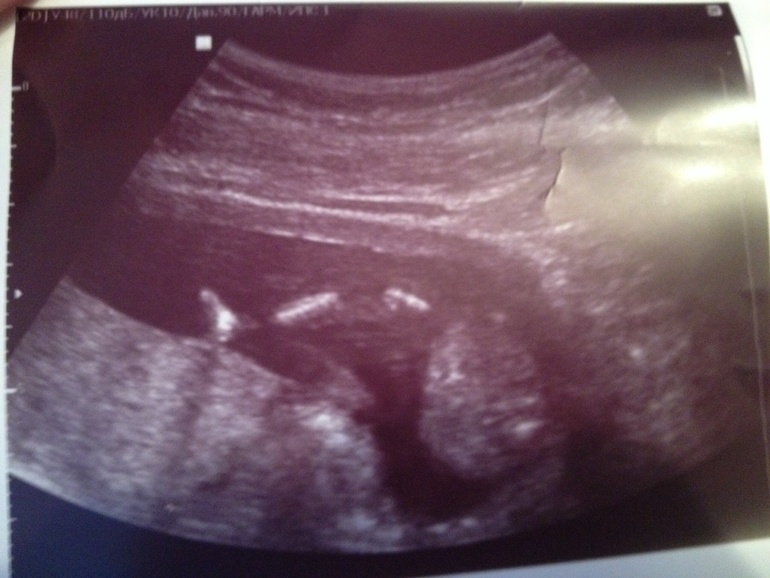

Алина 11 лет Доченька!!! Растем здоровые и длинные) Врач говорит, что родиться будущая модель) Мы очень ждем тебя, Маруся! Посмотрите еще 20 записей на эту тему Отменить Ответить Узи! Первые шевеления! Чаты Беременных Выберите чат: Январята-2026 Февралята-2026 Мартята-2026 Апрелята-2026 Майчата-2026 Июнята-2026 Июлята-2026 Августята-2026